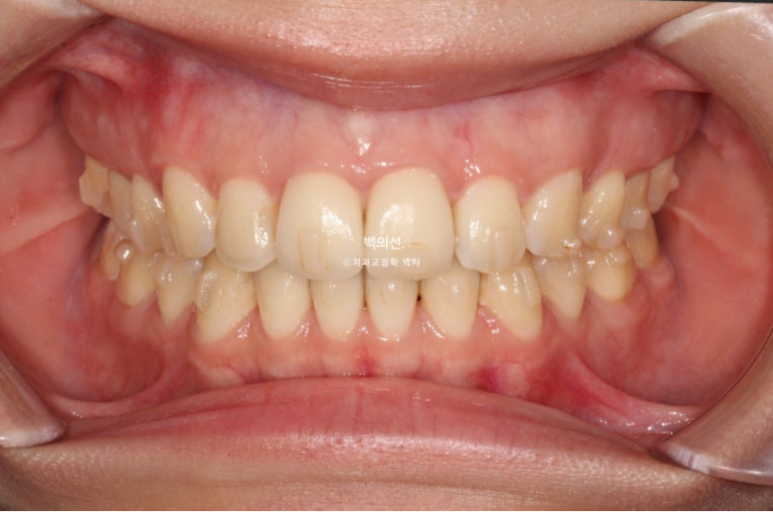

25.07

기울어져 보이던 측절치는 대칭성을 회복했으며

교합은 처음보다 좋아졌습니다.